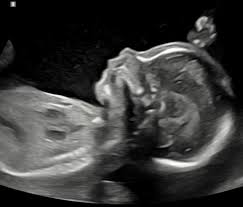

Our 2D ultrasound sessions are thoughtfully designed to offer a quiet moment of reassurance in those early weeks, before you can feel the comforting flutter of tiny kicks. It’s a beautiful opportunity to see your little one moving in real time, hear their precious heartbeat, with that first little perfect connection.

Whether you’re simply seeking that reassurance or hoping for a sweet little sneak peek to discover your baby’s gender and share the excitement with eager siblings awaiting a brother or sister, this experience is all about celebrating the joy of your growing family along with a little peace of mind.